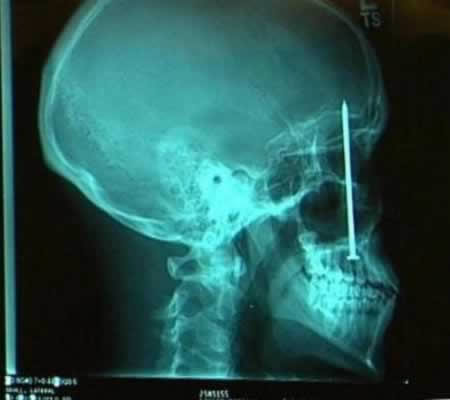

脳にダメージなければ意外と無事なのね

21はその後矢を引き抜いて飛び出た目玉を食べそう。

以前なんかで聞いた話だけど、米国で頭を鉄棒が貫通して

穴が開いた状態で運び込まれた人が居たそうだ。

その人はその後も生きてたそうだけど、人格が変わってしまったとか。